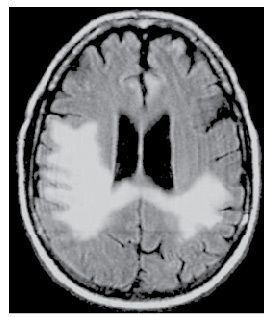

Quelle est la séquence de cette IRM? Quel diagnostic et pourquoi?

IRM séquence T2

HPN car dilatation tétra-ventriculaire, plage hyposignal T2 autour, et atrophie corticale modérée